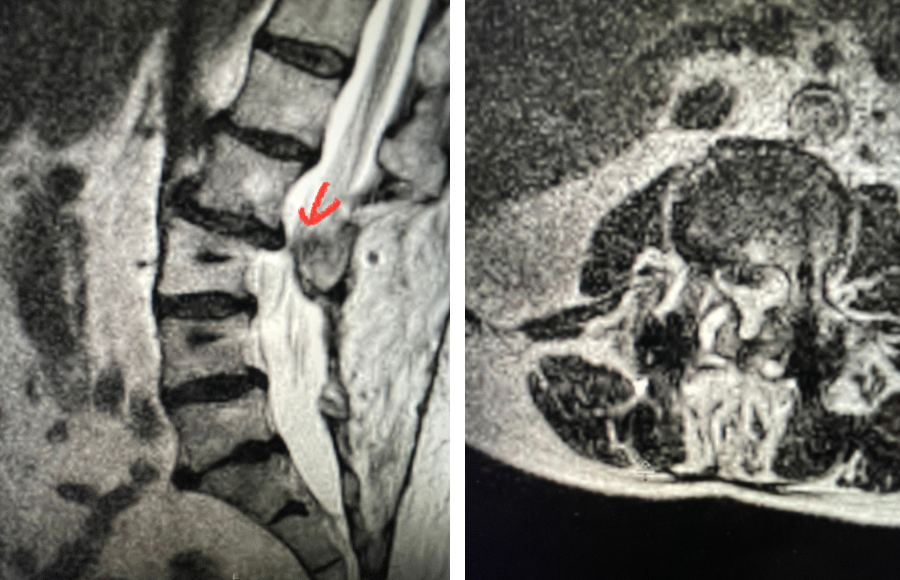

Fig 3: Sagittal CT scan with bone windows demonstrating an L5 pars defect (blue dot) and abnormal L5-S1 facet complex as well as a normal right pars structure of L5 (red dot).

Another interesting 54-year-old patient presented with low back pain and severe left lower extremity pain over two months. He had a history of falls. The pain in the leg was more bothersome to the patient. The patient had a work-up with an MRI and CT of the lumbar spine. MRI demonstrated a subtle grade 1 spondylolisthesis L5-S1 with a dysmorphic L5 vertebral body (Fig 2). There was a suggestion of a left L5 spondylolysis or defect in the bridge of bone that connects the superior facet process of the segment and the inferior facet process. A CT of the lumbar confirmed this unilateral abnormality which certainly could account for the patient’s left leg pain (Fig 3). This is an unusual finding in that most patients have bilateral pars defects. Patients with L5-S1 often have congenital abnormalities of the lumbosacral junction including weird shaped, elongated or dysplastic facet joints. A subtle L5-S1 spondylolisthesis with an associated smaller and misshapen L5 vertebral body is often associated with L5 spondylolysis. In addition, with a dysmorphic L5 vertebral body, there is secondary disc degeneration at L5-S1 and sometimes at the L4-5 disc with an associated retrolisthesis at L4-5. There is less surface to surface contact of the L4-5 and L5-S1 leading to chronic segmental instability.